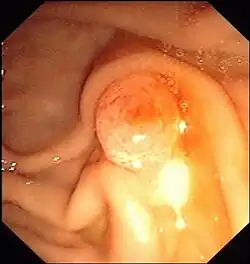

Mit einem durch den Mund (oral) eingeführten Endoskop mit Seitblickoptik, dem Duodenoskop, wird das Duodenum aufgesucht und die Vatersche Papille sondiert, die Mündung des gemeinsamen Ausführungsganges von Gallengang und Bauchspeicheldrüsengang. Das Kontrastmittel wird retrograd, also entgegen der normalen Flussrichtung der Gallenflüssigkeit, in die Gallenwege injiziert. Unter der Durchleuchtung mit Röntgenstrahlen werden Verengungen der Gänge, etwa durch Gallensteine, Gallengrieß oder Tumore, beurteilbar.

Vorteil der ERCP ist die Möglichkeit, neben der Diagnostik gleichzeitig auch zu therapieren, beispielsweise mit Hilfe eines über den Arbeitskanal des Endoskops vorgeschobenen Instruments zur Steinentfernung oder Zertrümmerung (Lithotripsie). Dabei werden Gallensteine, die von der Gallenblase in den Gallengang gerutscht sind und sich dann am eng zulaufenden Ende vor der Papille verkeilen, entfernt. Dies geschieht mit einem Dormia-Körbchen. Ist der Stein zu groß, um die aufgeschnittene oder erweiterte Papille zu passieren, erfolgt zuvor die Lithotripsie, entweder mechanisch oder mittels Laser.

Ist das Vorschieben der Instrumente in den Gallengang nicht möglich, wird die Papillenöffnung mit einem Papillotom, einem speziellen Katheter mit einem beweglichen elektrisch geladenen Draht, aufgeschnitten. Dieser Vorgang wird als endoskopisch ausgeführte Papillotomie (EPT) bezeichnet. Gelegentlich wird stattdessen auch eine Aufweitung der Papillenöffnung mit einem Ballon durchgeführt.